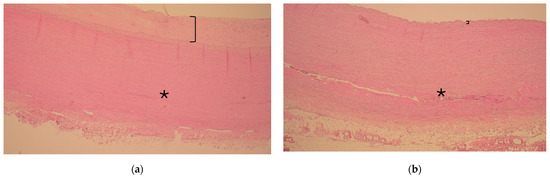

Survival probability (%) of patients after surgery for acute aortic type A dissection in patients with diabetes (blue line) compared with patients without diabetes (red line). Time-varying outcome according to Kaplan–Meier estimation. Log rank p = 0.187.

There were no statistical differences in outcome variables; altogether, strokes occurred in 38 patients (30.9%), 16 patients (13.0%) required dialysis after surgery for ATAAD, 16 patients had respiratory insufficiency, and there were 5 patients with heart failure. Reintervention included eight aortic root reinterventions, none of which had diabetes mellitus. The early 30-day mortality occurred in 17 patients (13.8%). During follow-up, 8 and 78 patients with and without diabetes died, respectively (Figure 2, logarithmic rank p = 0.187).

According to the adjusted multivariable Cox regression analysis, the presence of diabetes mellitus (hazard ratio [HR]: 0.69, 95% confidence interval [CI]: 0.21–2.23, p = 0.537) was not a significant factor related to all-cause mortality. Instead, age and high preoperative lactate levels were risk factors for all-cause mortality (HR: 1.05, 95% CI: 1.01–1.09, p = 0.019 and HR: 1.31, 95% CI: 1.14–1.50, p < 0.001, respectively; Table 5).